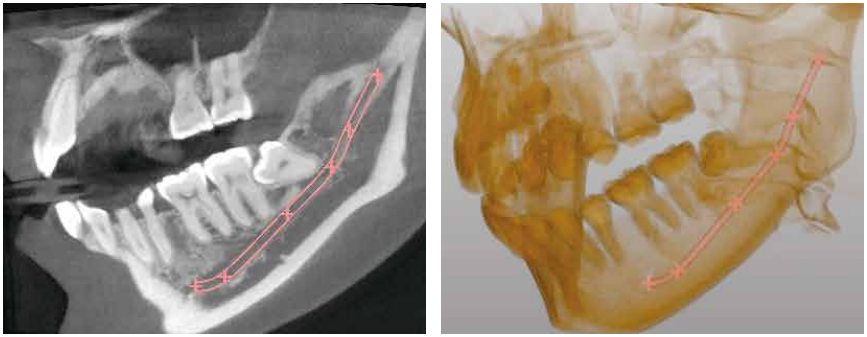

CT撮影による3D事前診断

危険な神経を正確に診断